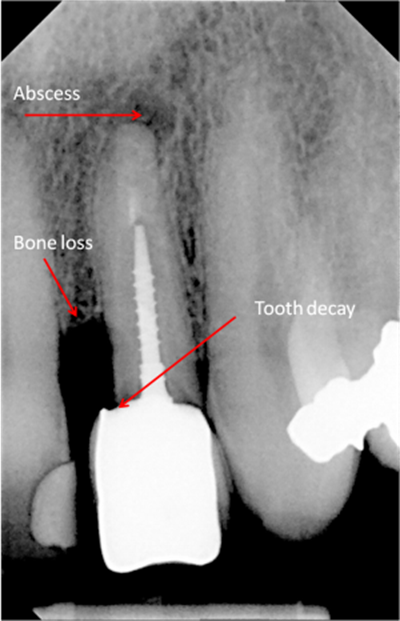

Digital x-rays can be used to diagnose:

• Cysts of jawbone

• Bone loss

• Cancerous and non-cancerous bony lesions

• Decay between teeth

• Development abnormalities

• Poor tooth and root positions

• Impacted teeth